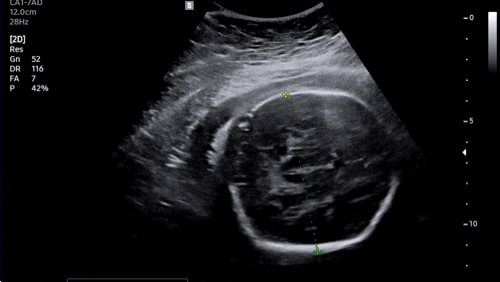

280데이즈 캡챠가 없네…?? 푸야로 대신한닷! ?34주차 증상? 1) 엘디군 태동이 배를 뚫고 나올 것...